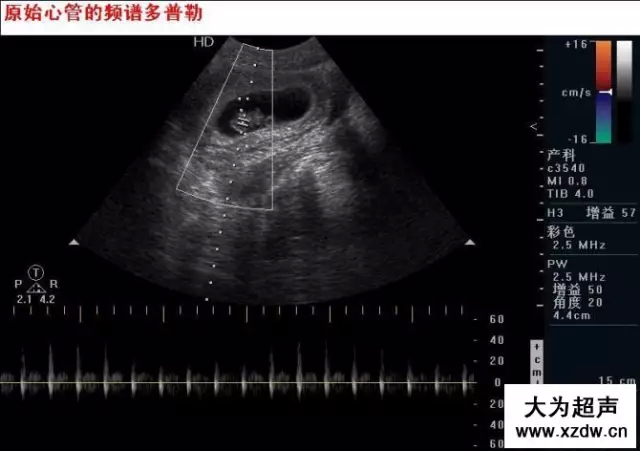

新領(lǐng)程大為超聲 早中孕期胎兒

產(chǎn)科超聲正常圖片